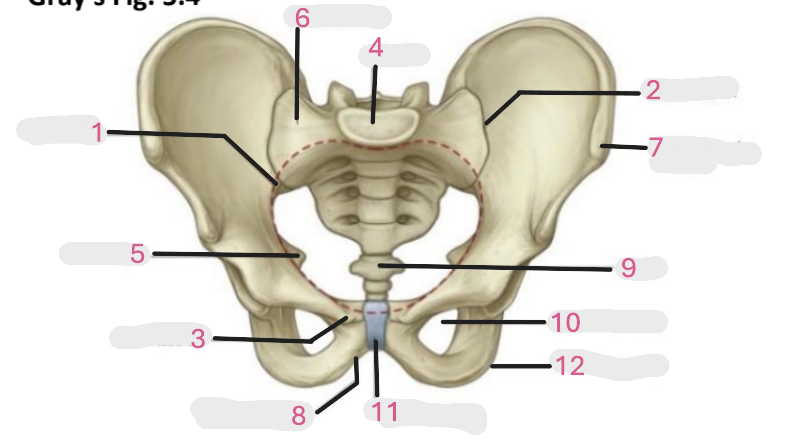

Where is the pelvic inlet

1

Where is the sacro-iliac joint

2

Where is the pubic tubercle

3

Where are the S1 body

4

Where is the ischial spine

5

Where is the ala of sacrum

6

Where is the anterior superior iliac spine

7

Where is the ischiopubic ramus

8

Where is the coccyx

9

Where is the obturator foramen

10

Where is the pubic symphysis

11

Where is the ischial tuberosity

12